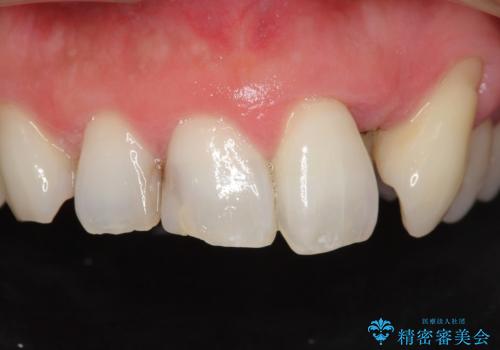

矯正治療とホワイトニングを提案しましたが希望されず、「接客関係の仕事で矯正治療は考えられない、短期間で治療を終わらせたい、ホワイトニングでは難しい位の人工的な白さにしたい」とのご要望により、治療前にワックスアップ模型を作製し何度もコンサルテーションを重ね、治療方針を決定しました。

歯頚ラインが変えられないことや天然歯を削るリスクをご理解頂いた上で、オールセラミッククラウンによる補綴治療を行いました。(見えない奥歯のみ天然歯のままとしました)

下の前歯1本だけ歯軸を変えるために神経をとり根管治療を行っております。

それ以外の歯は神経をとらずに済むよう、慎重かつ丁寧に歯の形態を整えました。

クラウンの色味・形態の修正や患者様のお仕事のご都合で来院できない期間があったことにより、予想より治療期間が長くなってしまいましたが、審美的な仕上がりにご満足頂けました。

クラウンの色味に関して、自然な白さ(シェードA1~NW0.5)のクラウンを作製・試適したところ「もっと白くしたい」と希望され、当院で最も明度の高い色(シェードNW0)に修正しました。

被せ物の種類:オールセラミッククラウン スタンダード (シェード:NW0)